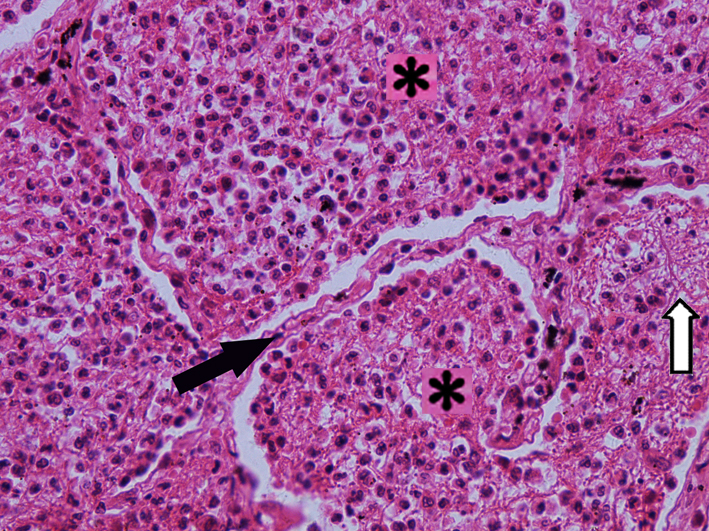

1.Labar pneumonia